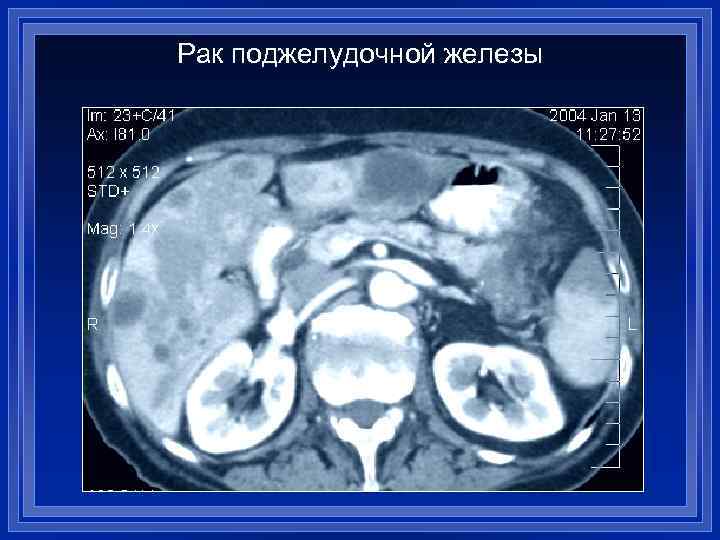

Рак поджелудочной железы